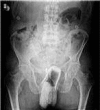

Results: All patients were males, and their mean age was 48 years (range, 33-68 years). The objects in the rectum of these 15 patients were an impulse body spray can (4 patients), a bottle (4 patients), a dildo (2 patient), an eggplant (1 patient), a brush (1 patient), a tea glass (1 patient), a ball point pen (1 patient) and a wishbone (1 patient, after oral ingestion). Twelve objects were removed transanally by anal dilatation under general anesthesia. Three patients required laparotomy. Routine rectosigmoidoscopic examination was performed after removal. One patient had perforation of the rectosigmoid and 4 had lacerations of the mucosa. None of the patients died.

Conclusions: Foreign bodies in the rectum should be managed in a well-organized manner. The diagnosis is confirmed by plain abdominal radiographs and rectal examination. Manual extraction without anaesthesia is only possible for very low-lying objects. Patients with high- lying foreign bodies generally require general anaesthesia to achieve complete relaxation of the anal sphincters to facilitate extraction. Open surgery should be reserved only for patients with perforation, peritonitis, or impaction of the foreign body.